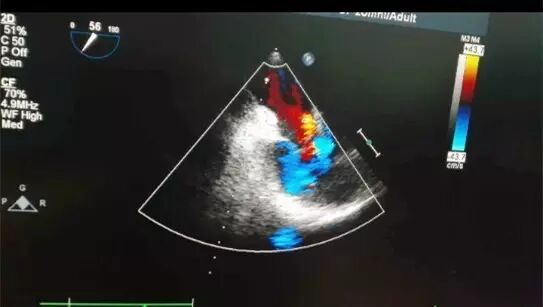

31岁的张女士是三月前怀孕时被检查出患有先天性心脏病,房间隔缺损,三尖瓣下移畸形,三尖瓣中大量返流,肺动脉高压,无奈下选择了终止妊娠。

经过4个多小时的奋战,手术顺利完成。术后复查心脏彩超,三尖瓣仅有极少量反流,手术很成功,同时也满足了患者再次妊娠的要求。